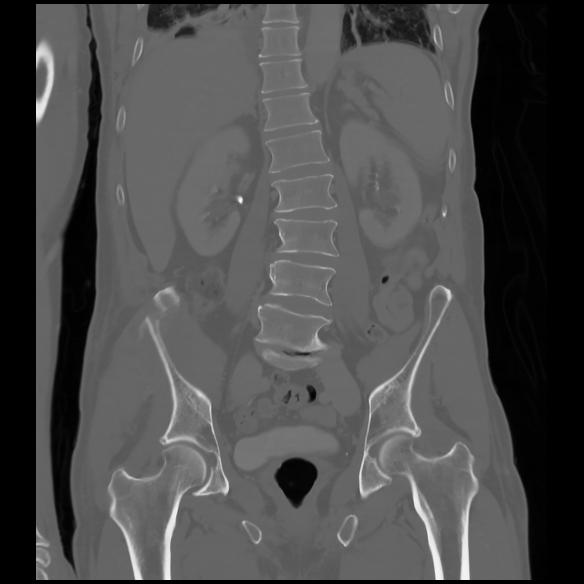

6 CUERPO,CE,Coronal,3.000,CUERPO,Coronal,